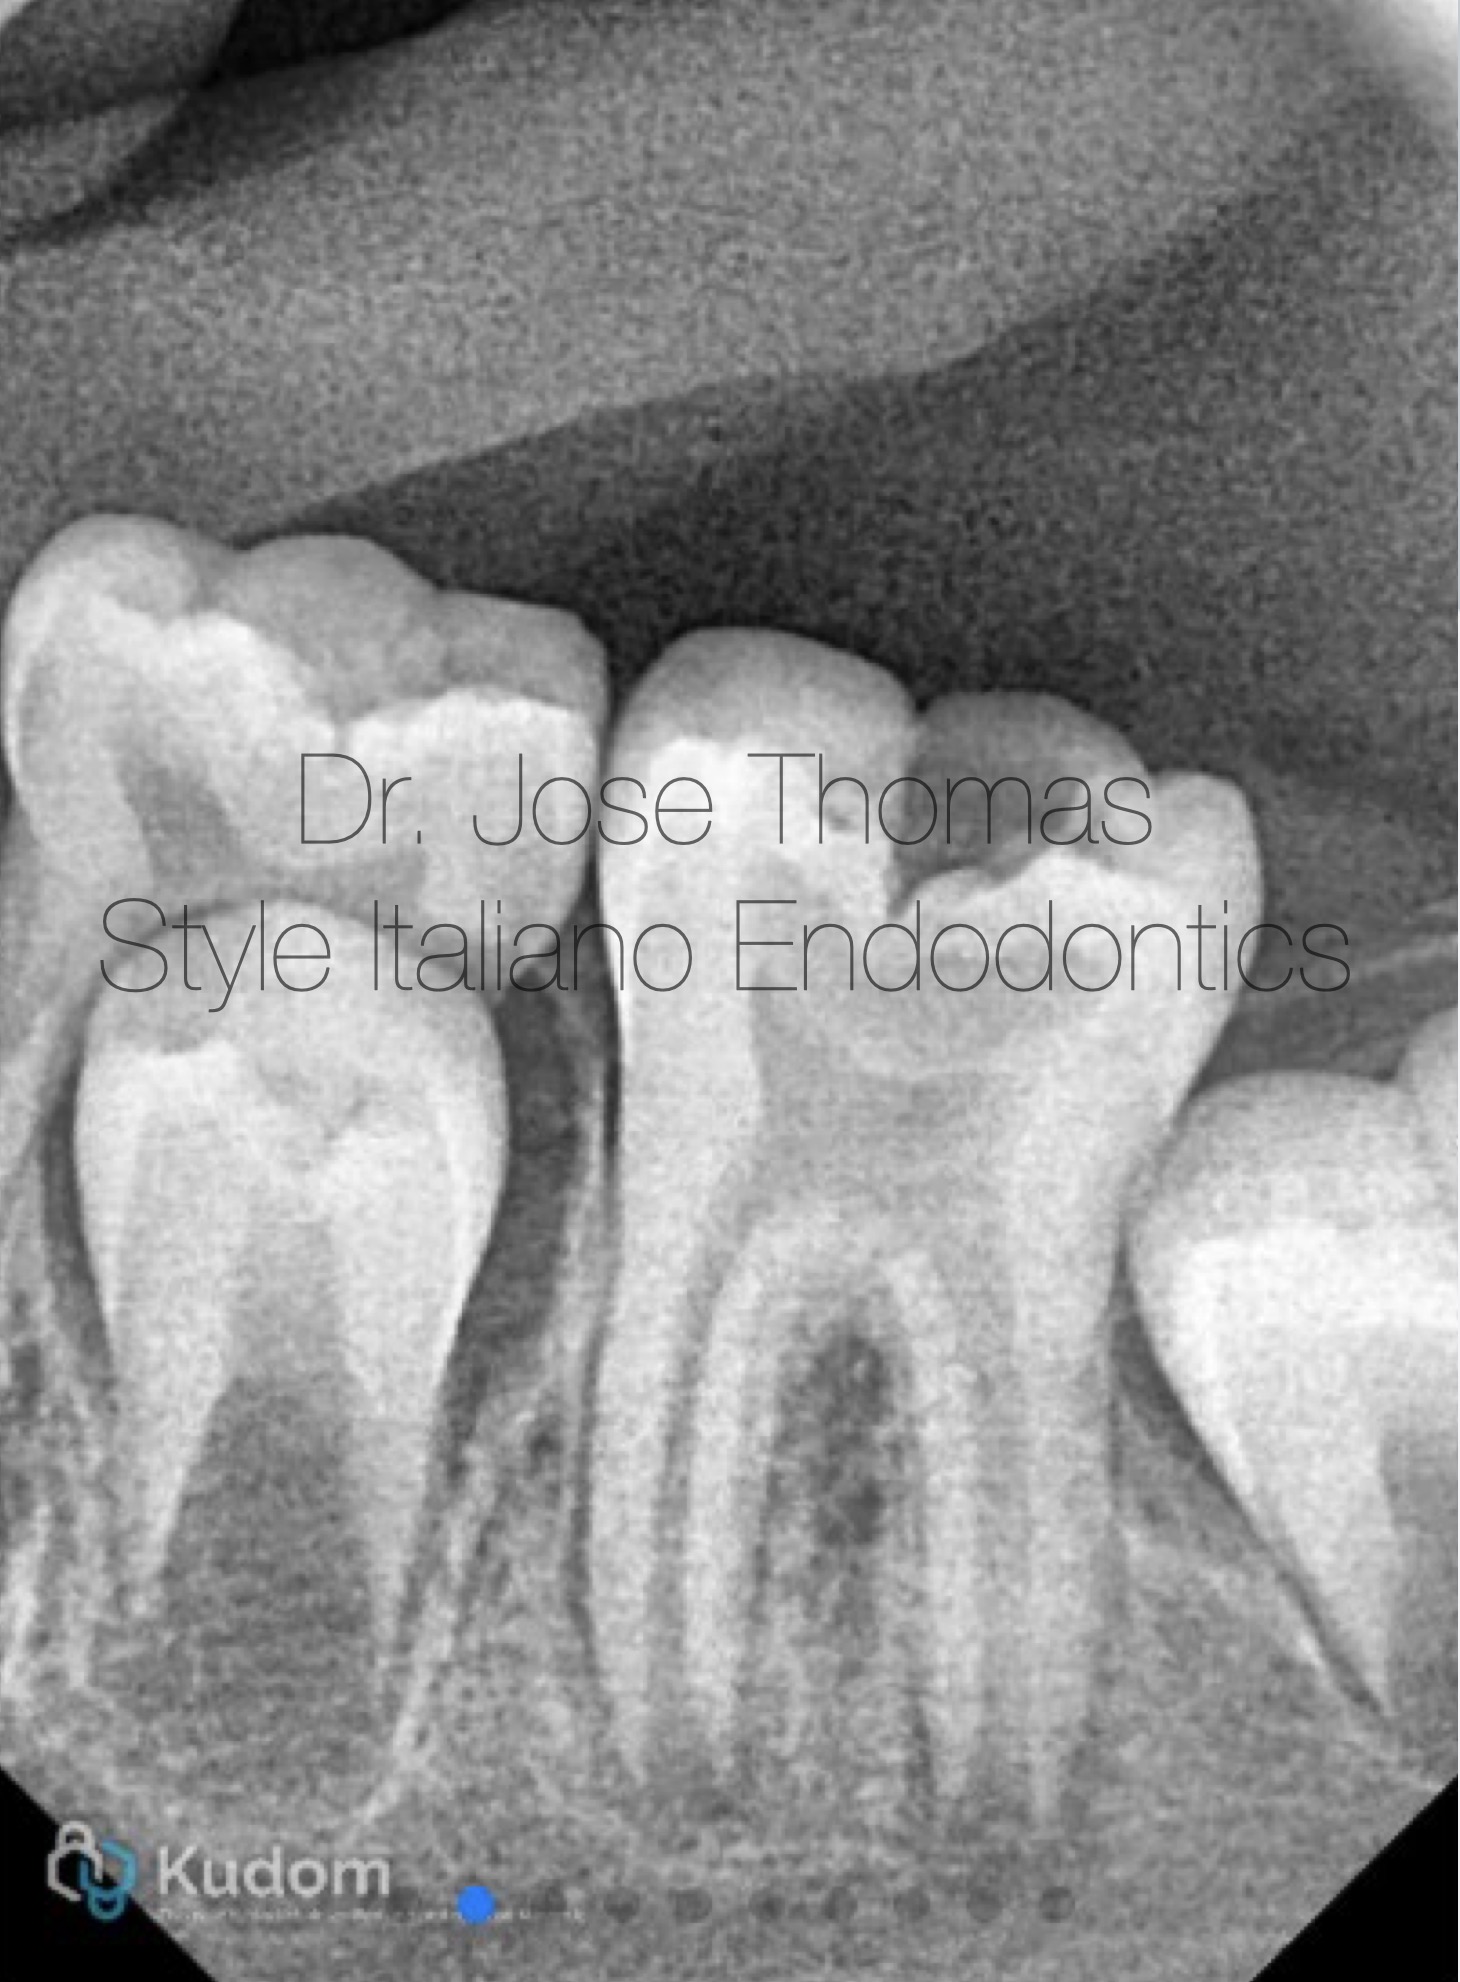

Fig. 1

Xray Shows deep carious lesion in tooth 36. The root length is nearly complete with wide open apical foramina and indistinct apical lamina dura around both mesial and distal roots.